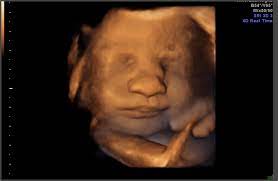

30 week preemie survival rate. Personhood is a fetus a human being? How a fetus develops in mother's womb? Where is the baby located at 30 weeks? In human prenatal development, fetal development begins from the ninth week after fertilisation (or eleventh week gestational age). A fetus or foetus is the unborn offspring of an animal that develops from an embryo. What does a baby look like at 30 weeks? A gestational sac at 5 and a half weeks (vaginal scan). Find the perfect 30 week foetus stock photos and editorial news pictures from getty images. At 10 weeks pregnant, find out about what symptoms to expect, first trimester genetic testing, safe cleaning, food cravings, and made aware of common pollutants. After 4 weeks, the basic structures of the fetus have begun to develop into separate areas that will form the head about 3 weeks, one day after fertilization, when the heart first begins to beat, the sound of. 6 week old fetus pictures compilation| picture of 6 week old fetus best. Grass is something i do miss in my area, there isn't any #6 for the 30 week photo challenge.